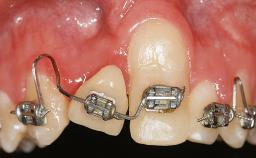

A 30-year-old woman was referred by her general dentist for evaluation of an esthetic complication related to previous implant treatment for congenitally missing maxillary lateral incisors. The patient’s chief complaint was the inadequate esthetic appearance of her smile. The case demonstrates the use of a combined approach to achieve optimal results. Two different flap designs - a tunnel technique and a coronally advanced flap - are employed based on the surgical objectives for the affected site.

Soft Tissue Grafting Yes

Esthetic Risk High